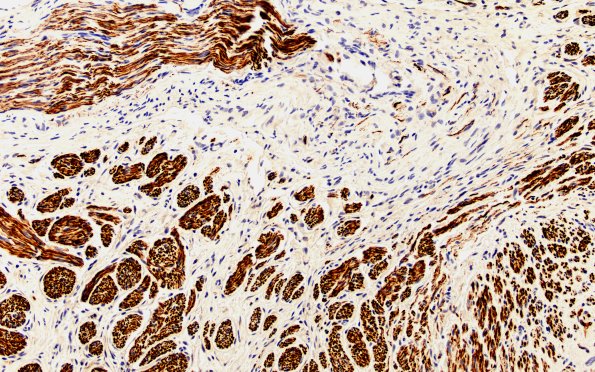

1B3 Neuroma, traumatic (Case 1) NF 20X

Axons are collected into mini-fascicles within some areas of the neuroma. (NF IHC)